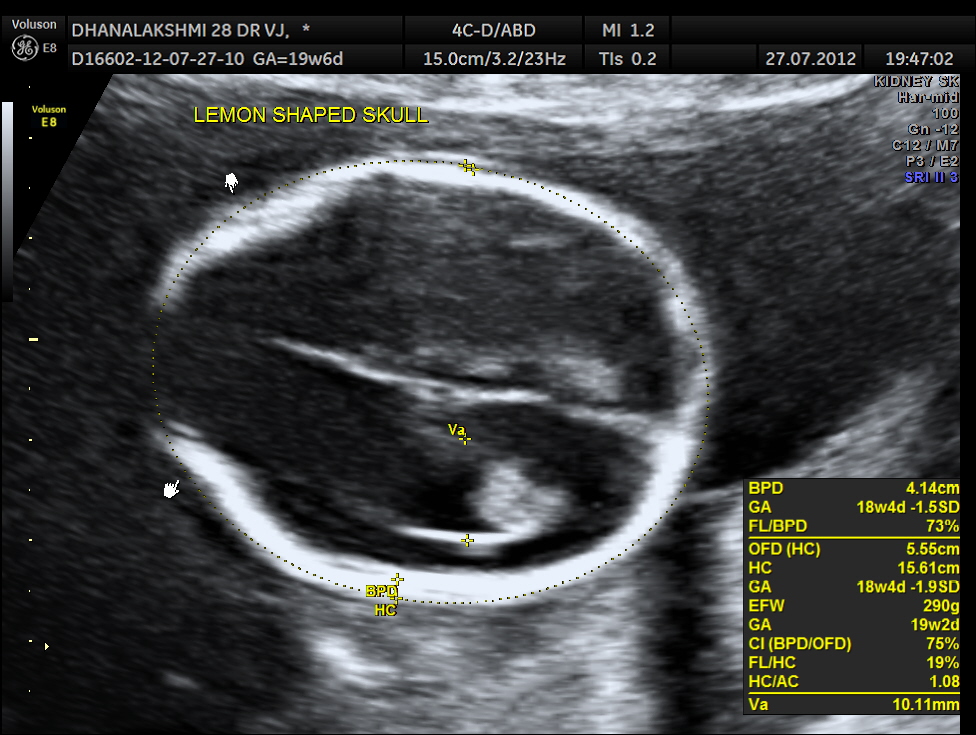

This was a 29 year old lady ; G3 P1 A1 ( MTP by choice) , referred for anomaly scan at 20 weeks. Earlier scan done at 15 weeks did not reveal any abnormality.But scan done 2 days ago at a different centre has revealed abnormal shape of head.

The following was the picture of the head showing the ” lemon sign”of the skull and the” banana sign “of the cerebellum.